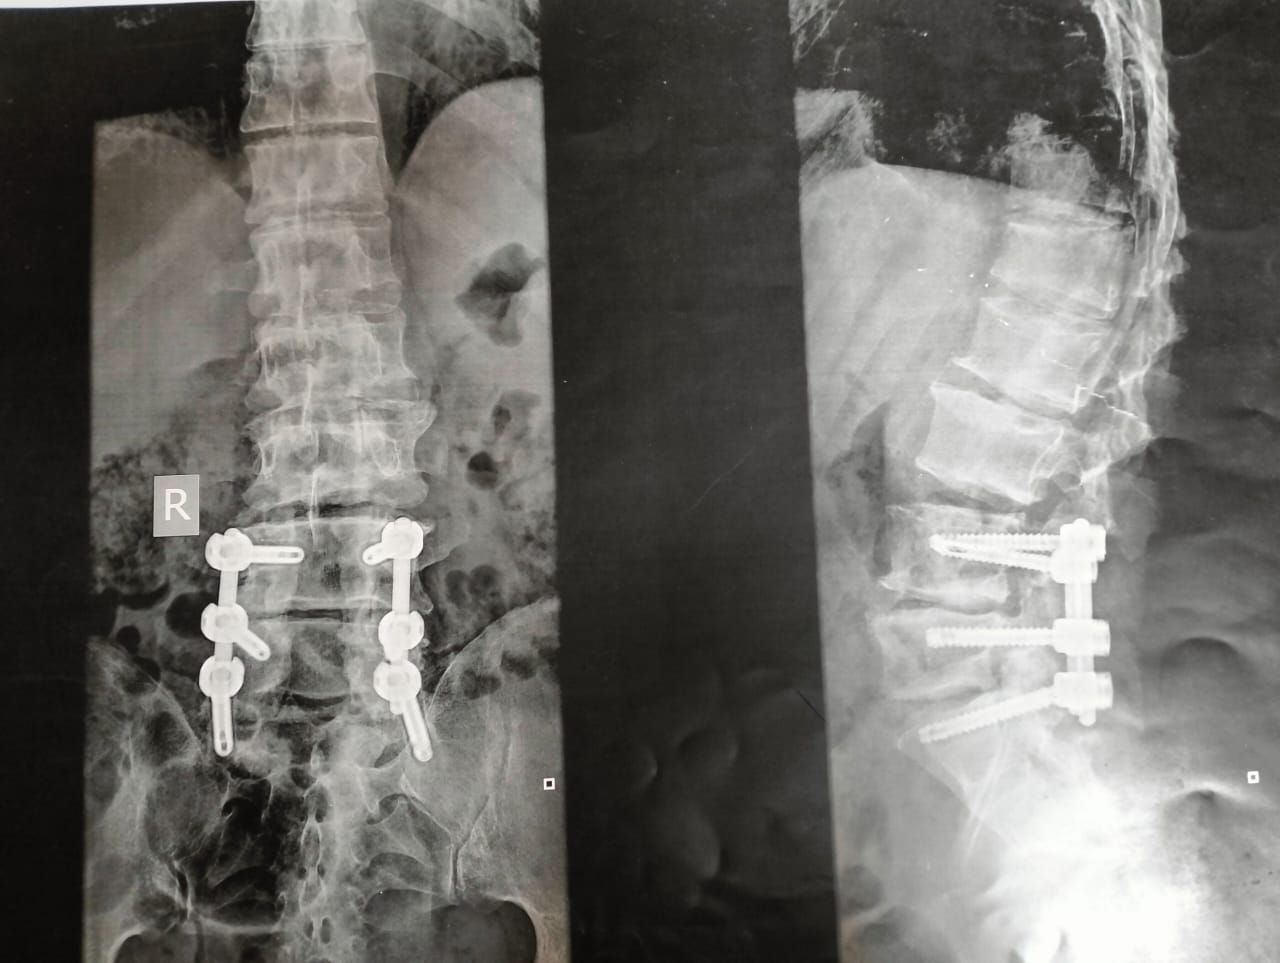

التقرير الطبى

صورة أشعة للمسن توضح الاصابات الناتجة بسبب الاعتداء